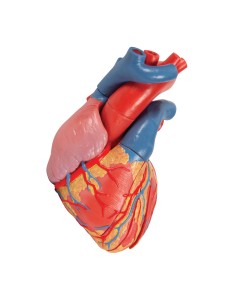

Du crâne en 22 parties à verrouillage magnétique aux modèles de colonne vertébrale, des modèles d'articulation aux modèles de cœur, chaque pièce de notre collection est conçue pour une immersion totale dans l'étude de l'anatomie humaine. Nos modèles, réalisés à partir de scans d'os réels, garantissent une expérience tactile authentique et une fidélité de poids presque identique aux originaux.

Indispensables aux étudiants comme aux professionnels, nos modèles anatomiques sont des outils pédagogiques qui permettent d'observer les structures anatomiques avec précision, en évitant les dissections ou les études invasives. Ils sont également utiles pour expliquer les pathologies aux patients, ce qui rend la communication plus efficace et permet de gagner un temps précieux.